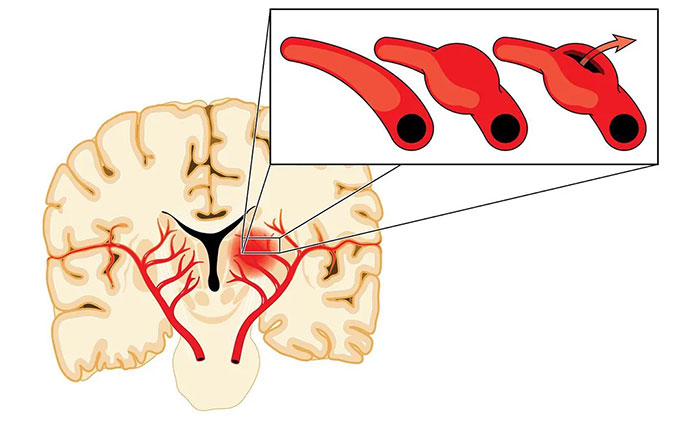

烟雾病的本质是脑血管主干(颈内动脉和大脑中动脉)的狭窄和闭塞,导致灌注异常,引起脑细胞缺血,同时又伴以代偿性颅内异常新生小血管。这些烟雾状血管毕竟不是原始正常的血管,壁很薄,容易破裂出血,这就是烟雾病既容易引起脑梗死,又容易出血的原因。

根据《烟雾病治疗中国专家共识》,目前对于烟雾病主要采取药物保守治疗和外科手术治疗。其中,药物主要是用于对症支持治疗或围手术期管理。主要目的是为了防止脑血栓形成并维持足够的脑血容量,以及针对患者症状(如头痛、癫痫)给予相应药物治疗。

手术则是目前最主要的烟雾病治疗方式,可分为直接血运重建术、间接血运重建术以及联合(直接+间接)血运重建术。手术治疗的目的,是使用来自颈外动脉系统的血液供应来增加颅内血流,从而改善脑血流量和脑血流储备能力。

“这就好比‘南水北调’,黄河水情不足时,就从长江引流,支援北地,缓解缺水局面。”宫卫东主任形象地打了个比方,通过手术建立由脑外血管向脑内供血的通路,改善脑内血流。脑血供改善以后,对于烟雾状血管的供血需求会逐渐减少,从而降低再次发生脑缺血和脑出血的风险,改善患者的预后。